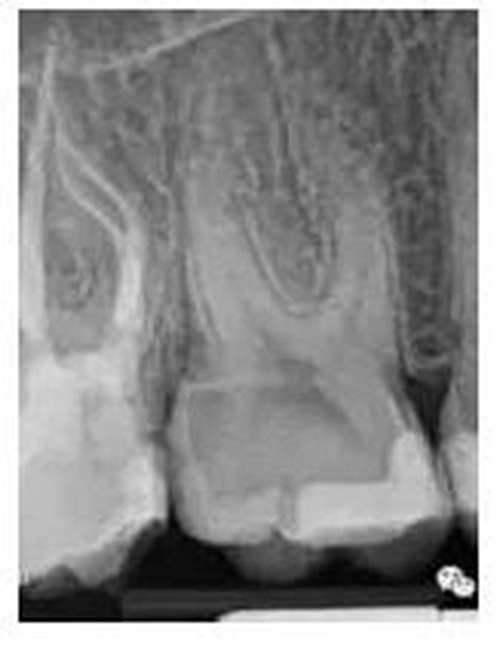

我的病例1_冠部處理成直線通道后的充填效果

我的病例2_下頜7"C"型根管的充填效果